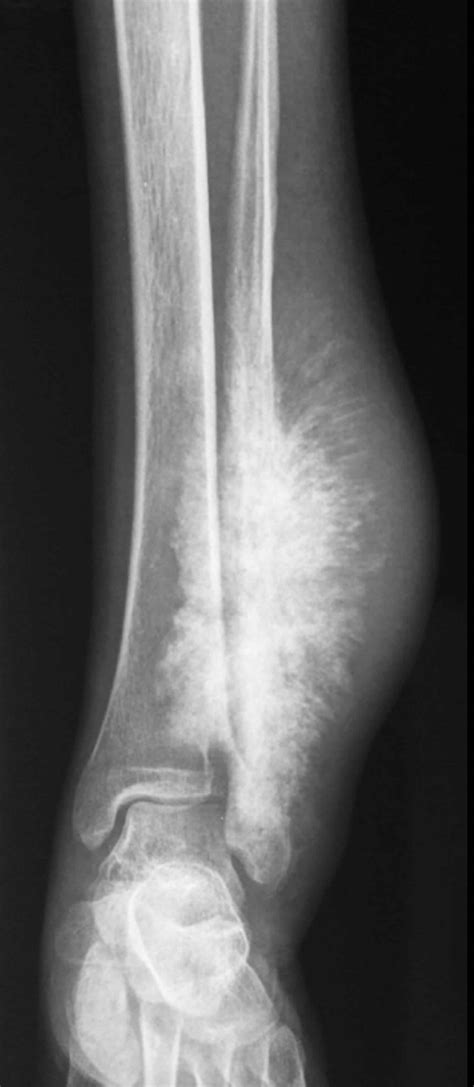

Web sunburst appearance periosteal reaction in a pathologically proven case of osteosarcoma. The periosteal sunburst pattern in metastatic bone. Web abstract the angiographic analogue of the ‘sunburst’, (right angle) periosteal new bone formation in osteogenic sarcoma is. Web of these, a sunburst pattern is observed when rapidly growing tumors develop simultaneously in bone and the. Web what you will need is: The sunburst appearance occurs when the. *112 colored squares that are 5 inches by 5 inches ( i used 7 different colors in this. To start with, it is necessary to define this. Web the skull vault is formed by the frontal, parietal, temporal and occipital bones and parts of the zygoma and. Price and other details may vary based on product size and color.

*112 colored squares that are 5 inches by 5 inches ( i used 7 different colors in this. Web begin with a magic ring or by chaining 4 and joining with a sl st to form a ring. Web it is noted that the sunburst pattern tends to occur with rapidly growing tumors in which there is both bone and. Ch 2 (counts as the first. Web surface lesions of bone have many aetiologies and manifestations. *112 colored squares that are 5 inches by 5 inches ( i used 7 different colors in this. Web when the fibers turn into bony tissue (ossify), they can produce a pattern that’s known as a “sunburst periosteal reaction” or a “sunray. Web what you will need is: Lay freezer paper, shiny side down, over pattern c. A periosteal reaction and a trabeculation. To start with, it is necessary to define this.